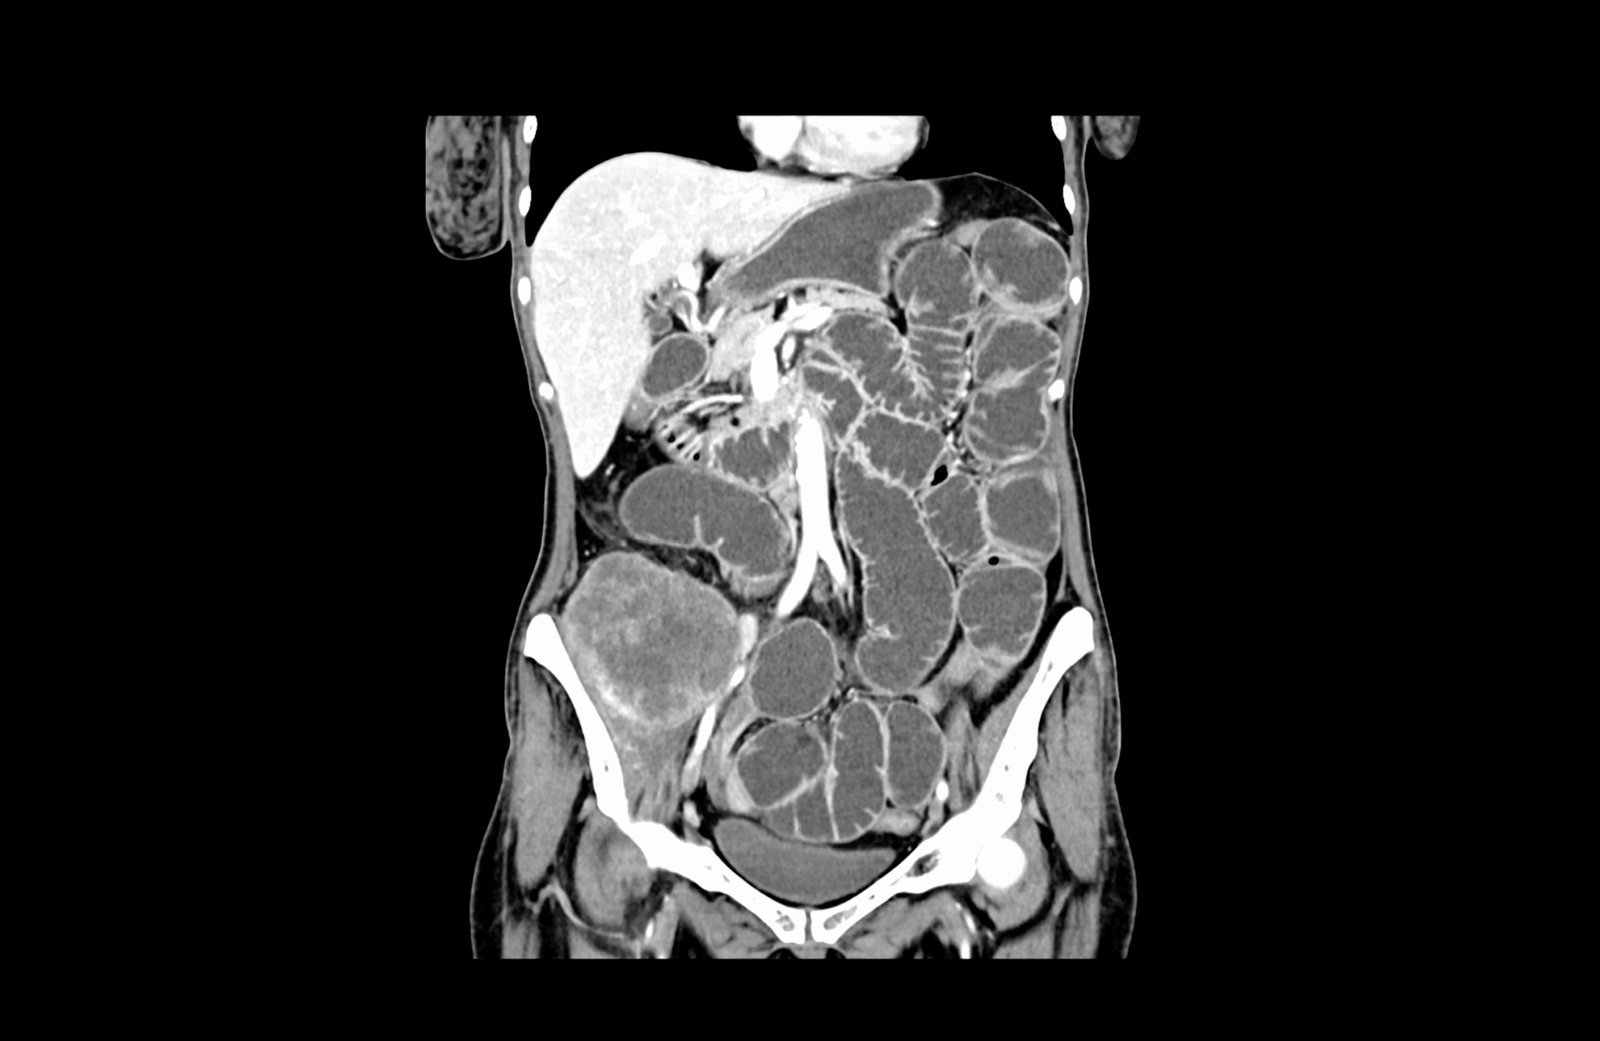

Извърши се компютърна томография на корем и малък таз, която установи:

- локално авансирала туморна формация на десния колон с огромни размери

- механичен илеус с пълен стоп в дисталния отдел на тънките черва с прераздути и оточни тънкочревни бримки, по цялата им дължина

Авансирала туморна формация на десния колон, на фона на силно раздути тънкочревни бримки, в условията на механичен илеус